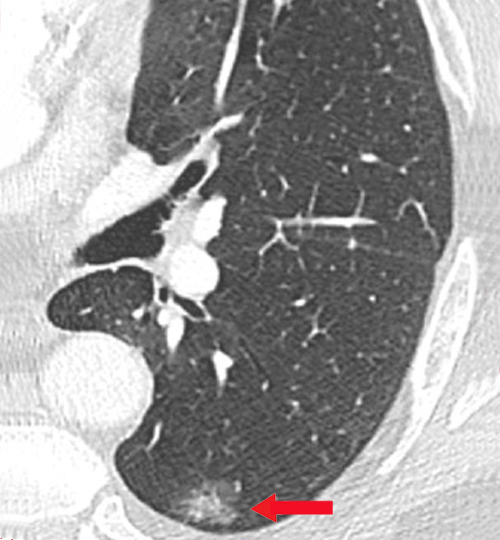

Les cancers du poumon sont la première cause de mortalité par cancer chez l’homme et probablement bientôt chez la femme. Les études montrent que le dépistage par scanner thoracique à faible dose chez des fumeurs actifs ou anciens asymptomatiques diminue la mortalité par cancer bronchopulmonaire de 24 à 33 %. Le rapport bénéfice/risque est favorable à condition de respecter les critères d’éligibilité et les modalités de surveillance ultérieure (en cas de découverte d’un nodule). Que faire en MG ?